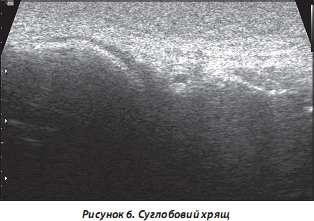

6. Суглобовий хрящ (СХ) (типовий приклад — структури менісків колінного суглоба). У нормі виглядає гіперехогенним унаслідок великої кількості різноспрямованих колагенових волокон (рис. 6).